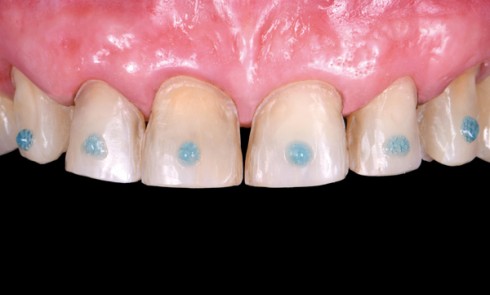

Article réservé à nos abonnés Les facettes en céramique : les clés du succès – Partie 1

La demande esthétique croissante des patients se traduit par une augmentation du nombre de consultations ayant pour objectif la réhabilitation...